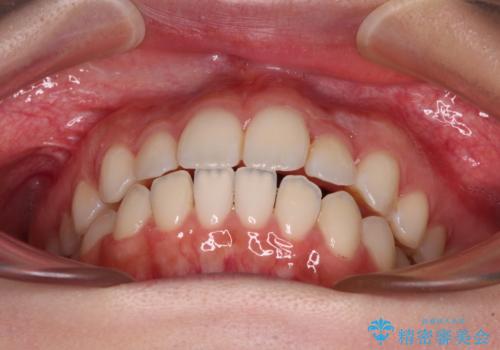

- 前歯のデコボコとクロスバイトを気にして来院された患者様です。

上顎側切歯(上の真ん中から2番目の歯)が舌側転位している場合、インビザラインでは仕上げきれないことが多く、更には無理して動かそうとすると歯髄壊死を起こすリスクが高いと言われています。

今回は、ワイヤー装置を併用することなく、インビザライン単体で矯正治療を行うこととしました。